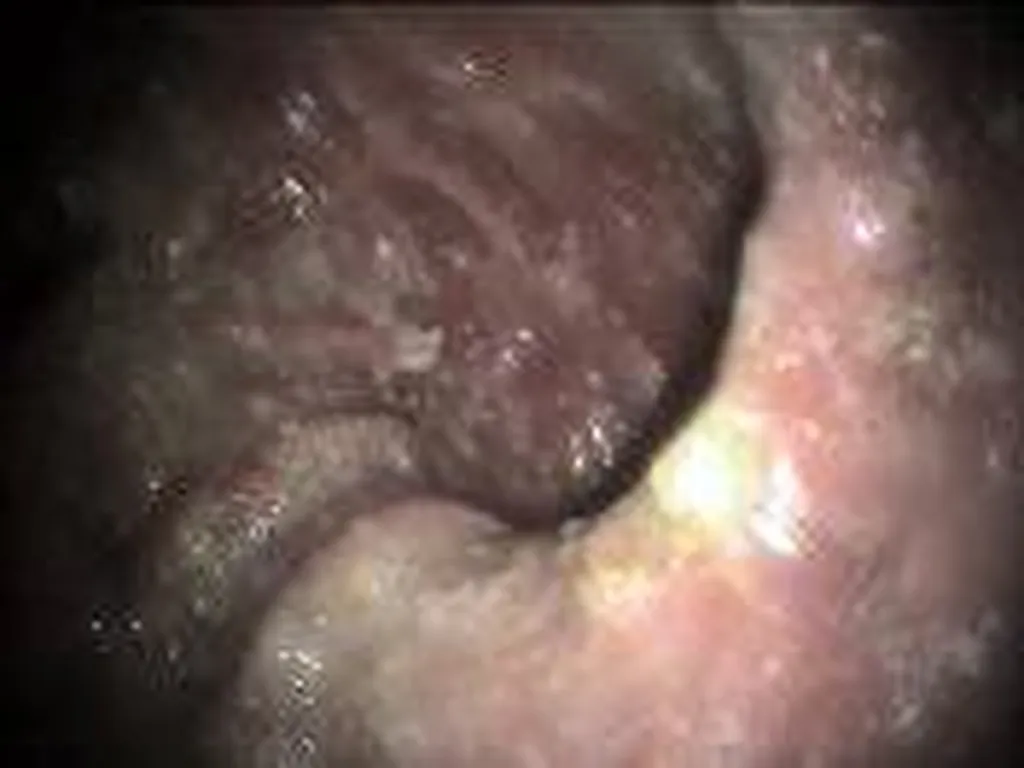

Une endoscopie consiste à l’utilisation d’une caméra afin de visualiser des structures, affections non accessibles facilement.

De nombreuses indications existent en endoscopie  que ce soit pour intervenir (retrait de corps étrangers), effectuer une biopsie (en cas de masse, tumeur),  visualiser (dilatation, lésion inflammatoire, ulcérée)

Affection touchant le système digestif (oesophagoscopie, gastroscopie, duodenoscopie, coloscopie) : corps étranger, mega-œsophage, gastrite aigue ou chronique, colite.

Des clichés sont effectués tout au long de l’intervention afin que vous puissiez visualiser les affections notées au cours de l’examen.